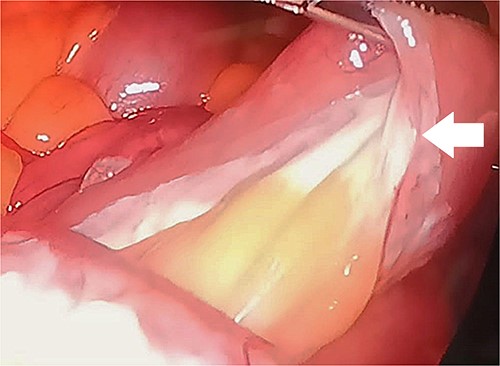

Upon examination, she had normal vital signs. Abdominal examination revealed a mildly distended and generally soft abdomen with tenderness in the upper quadrants. Bowel sounds were reduced. Lab tests showed a significantly elevated C-reactive protein level of 265 mg/dL (normal range: <0.3 mg/dL). Axial CT scan revealed mesenteric edema, jejunal wall thickening, surrounding fat stranding, and an enlarged mesenteric lymph node (Fig. 2). An emergent diagnostic laparoscopy revealed a mildly dilated viable jejunal loop, ~16 cm in length, located 10-cm distal to the ligament of Treitz. Additionally, a milky jejunal mesentery and a moderate amount of chalky ascitic fluid in perihepatic, perisplenic, and pelvic regions were observed (Fig. 3). Fluid analysis confirmed chylous ascites with a triglyceride level of 320 mg/dL (normal range: <110 mg/dL). Histopathological analysis of an excisional biopsy revealed abnormally dilated lymph vessels, leading to a diagnosis of cavernous mesenteric lymphangioma with chylous ascites. Surgical excision was not pursued because of the patient’s aggressive metastatic CUP state. She had an uneventful postoperative course, discharged on the fourth day, and was referred for follow-up with the oncology team for palliative chemotherapy.

Laparoscopic findings demonstrate a milky or whitish jejunal mesentery (arrow).